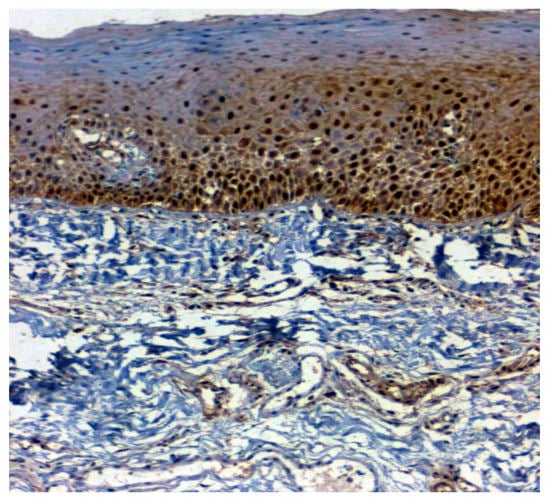

The expression of 14-3-3ε was studied in 130 patients, of which 81.5% (106/130) were found to be expressing 14-3-3ε. There was a significant correlation (p = 0.000; χ2 = 33.600) with expression among normal vs. OSMF vs. OSMF vs. OSCC patients. Table 4 shows the details of 14-3-3ε expression, which correlated with clinicopathological parameters. We found a statistically significant overexpression (p = 0.019; χ2 = 5.496) with increased age (>43 years), atrophic epithelium (p = 0.011; χ2 = 13.149) and increased degrees of inflammation (p = 0.041; χ2 = 8.252). Figure 7 shows the negative immunoexpression of 14-3-3ε in normal samples. Figure 8 shows the 14-3-3ε-positive immunoexpression in epithelial cells in OSMF samples, with cytoplasmic and nuclear positivity. In OSCC samples, 14-3-3ε demonstrates strong cytoplasmic and nuclear positivity in malignant epithelial cells (Figure 9).

Figure 8.

IHC for 14-3-3ε in OSMF samples (under 20× magnification).

Figure 9.

IHC for 14-3-3ε in OSCC samples (under 20× magnification).